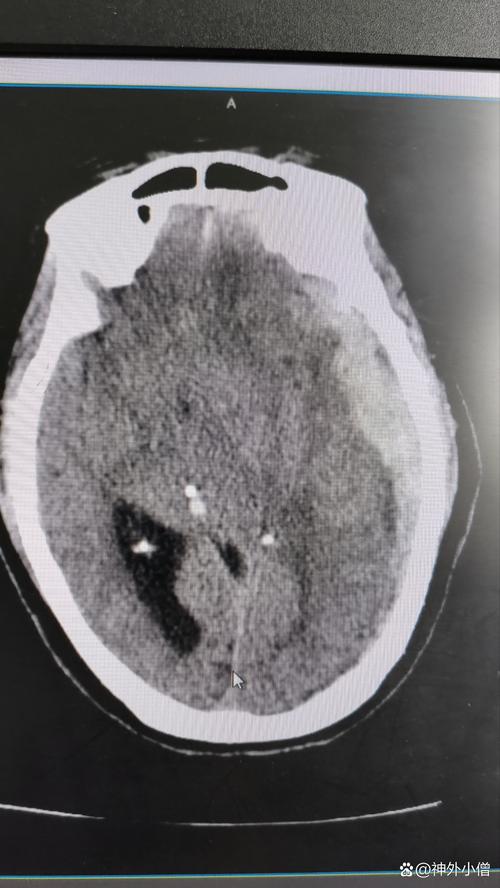

- 影像科: CT和MRI(磁共振)是诊断脑卒中的“金标准”,通过影像检查,医生可以在几分钟内明确是脑梗还是脑出血,为后续治疗争取宝贵时间。

- 影像检查: 立即进行头颅CT,这是最快区分脑出血和脑梗的方法,CT对出血非常敏感,但对超早期的脑梗可能不显示,如果高度怀疑是脑梗,可能会加做MRI-DWI(磁共振弥散加权成像),能更早发现梗死病灶。

- 如果是脑出血: 医生会评估出血量、位置以及是否影响生命中枢,如果出血量大或持续出血,会由神经外科评估是否需要开颅手术或微创穿刺引流来清除血肿,降低颅内压。